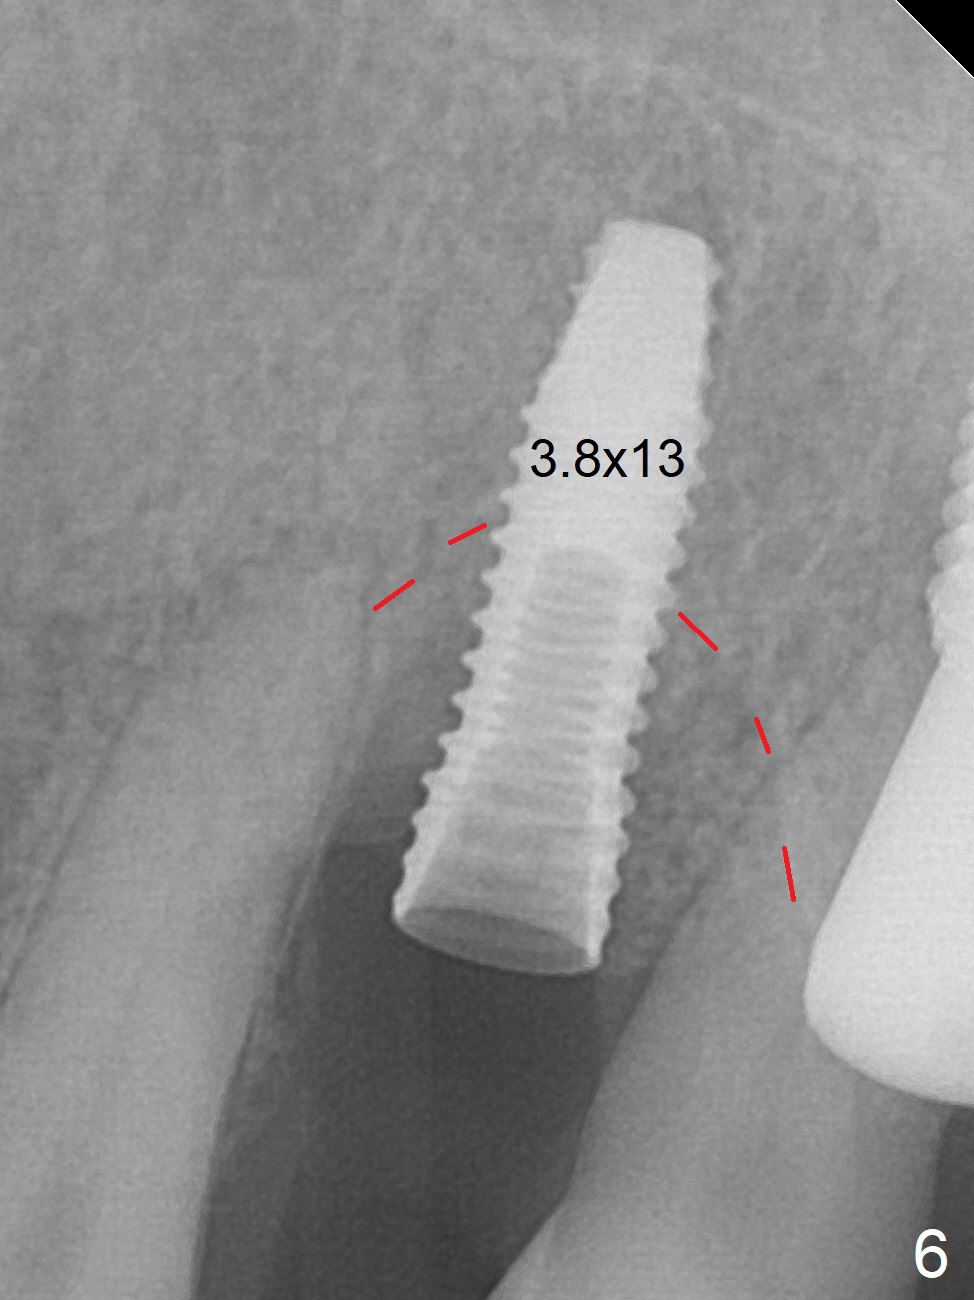

A few days prior to surgery, the tooth #12 developed abscess, self controlled by water pik (Fig.1 *). The buccal plate is defective. Initial osteotomy is close to the root of the tooth #11 (Fig.2). After adjustment of the trajectory and the depth of osteotomy (Fig.3), a 3.8x15 mm dummy implant is placed (Fig.4,5). In spite of a shorter implant (3.8x13 mm) placed deeper, approximately 7 mm implant threads are not covered buccally by the native bone (Fig.6 red dashed line). If the implant were placed deeper, the crown/implant ratio would become more unfavorable (abutment screw loosening, Fig.7). Since a mill abutment (4.5(2) mm) is inserted before Vanilla Graft, the deepest portion of the socket is unfilled (Fig.7 *). With meticulous use of a long explorer and additional allograft, the space is closed (Fig.8 *). The buccal plate collapses with apparently fistula formation 2 months postop. The patient removes the provisional for cleaning. It appears that the mill abutment is buccally placed and needs heavy reduction. The mill abutment is loose 2 months 10 days postop. When it is retightened, it tilts distal. Bone remains around the implant 6 months postop (Fig.9). Without a provisional at #12 for 5 months, the tooth #13 appears to have been shifted mesially (Fig.10 arrow). The mill abutment at #12 changes to a healing one. A lingual button is placed in the mesial surface of #13. Splinted provisional is fabricated with supraocclusion at #14 and 15 as an anchor (implants). The tooth #13 is being distalized with power chains. Limited ortho is finished nearly 2 months post banding (Fig.15,16).